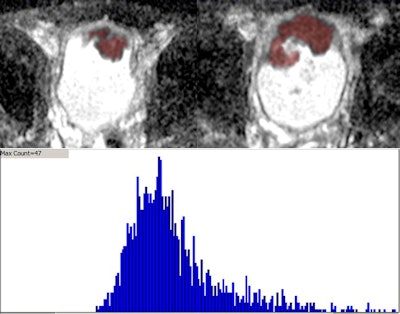

From these images, the researchers created ADC maps on a voxel-by-voxel basis for analysis using a standard monoexponential approach. They placed a volume of interest on all slices on the ADC map that encompassed each lesion, measuring whole-lesion mean ADC, kurtosis, and skewedness of ADC. They then compared this with T stage and pelvic nodal status at cystectomy, and later with subsequent metastasis in the 20 patients who presented for follow-up.

One limitation of ADC has been the method of evaluating it: Traditionally, a single region of interest is placed somewhere on the tumor in a single image slice, but this technique is prone to sampling error and incomplete evaluation, the study team wrote. The whole-lesion ADC histogram used for the current study requires placing a volume of interest that encompasses the tumor on every image slice on which it appears, providing a more sophisticated and comprehensive assessment, including metrics that examine lesion texture.

The group used in-house software called FireVoxel, which "was helpful for doing the whole-lesion evaluation, as well as for obtaining the histogram metrics," Rosenkrantz said. The software's capabilities for efficiently measuring the various parameters of a histogram aren't available on a standard PACS, but its functionality could generally be recreated by an experienced programmer, he noted.